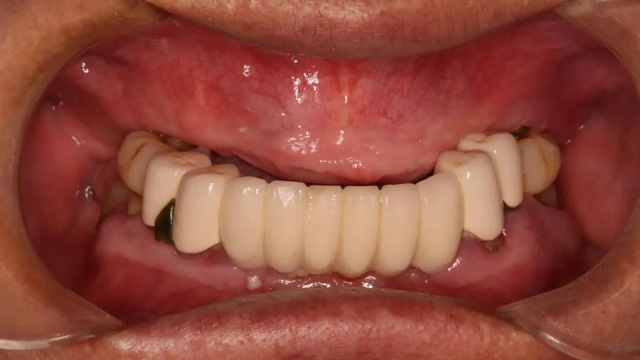

王先生全口種植后戴冠

按此方案,王先生只接受了一次手術(shù),就完成了松動(dòng)的種植體拆除和拔牙、種牙、戴臨時(shí)牙冠等一系列的治療,一次解決了困擾多年的缺牙問題。